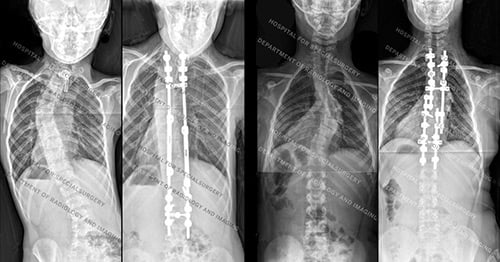

Posteroanterior (back-to-front) X-rays of dystrophic (first image) and nondystrophic scoliosis (second image)

Posteroanterior (back-to-front) X-rays of dystrophic scoliosis (first image) and nondystrophic scoliosis (second image) after surgery